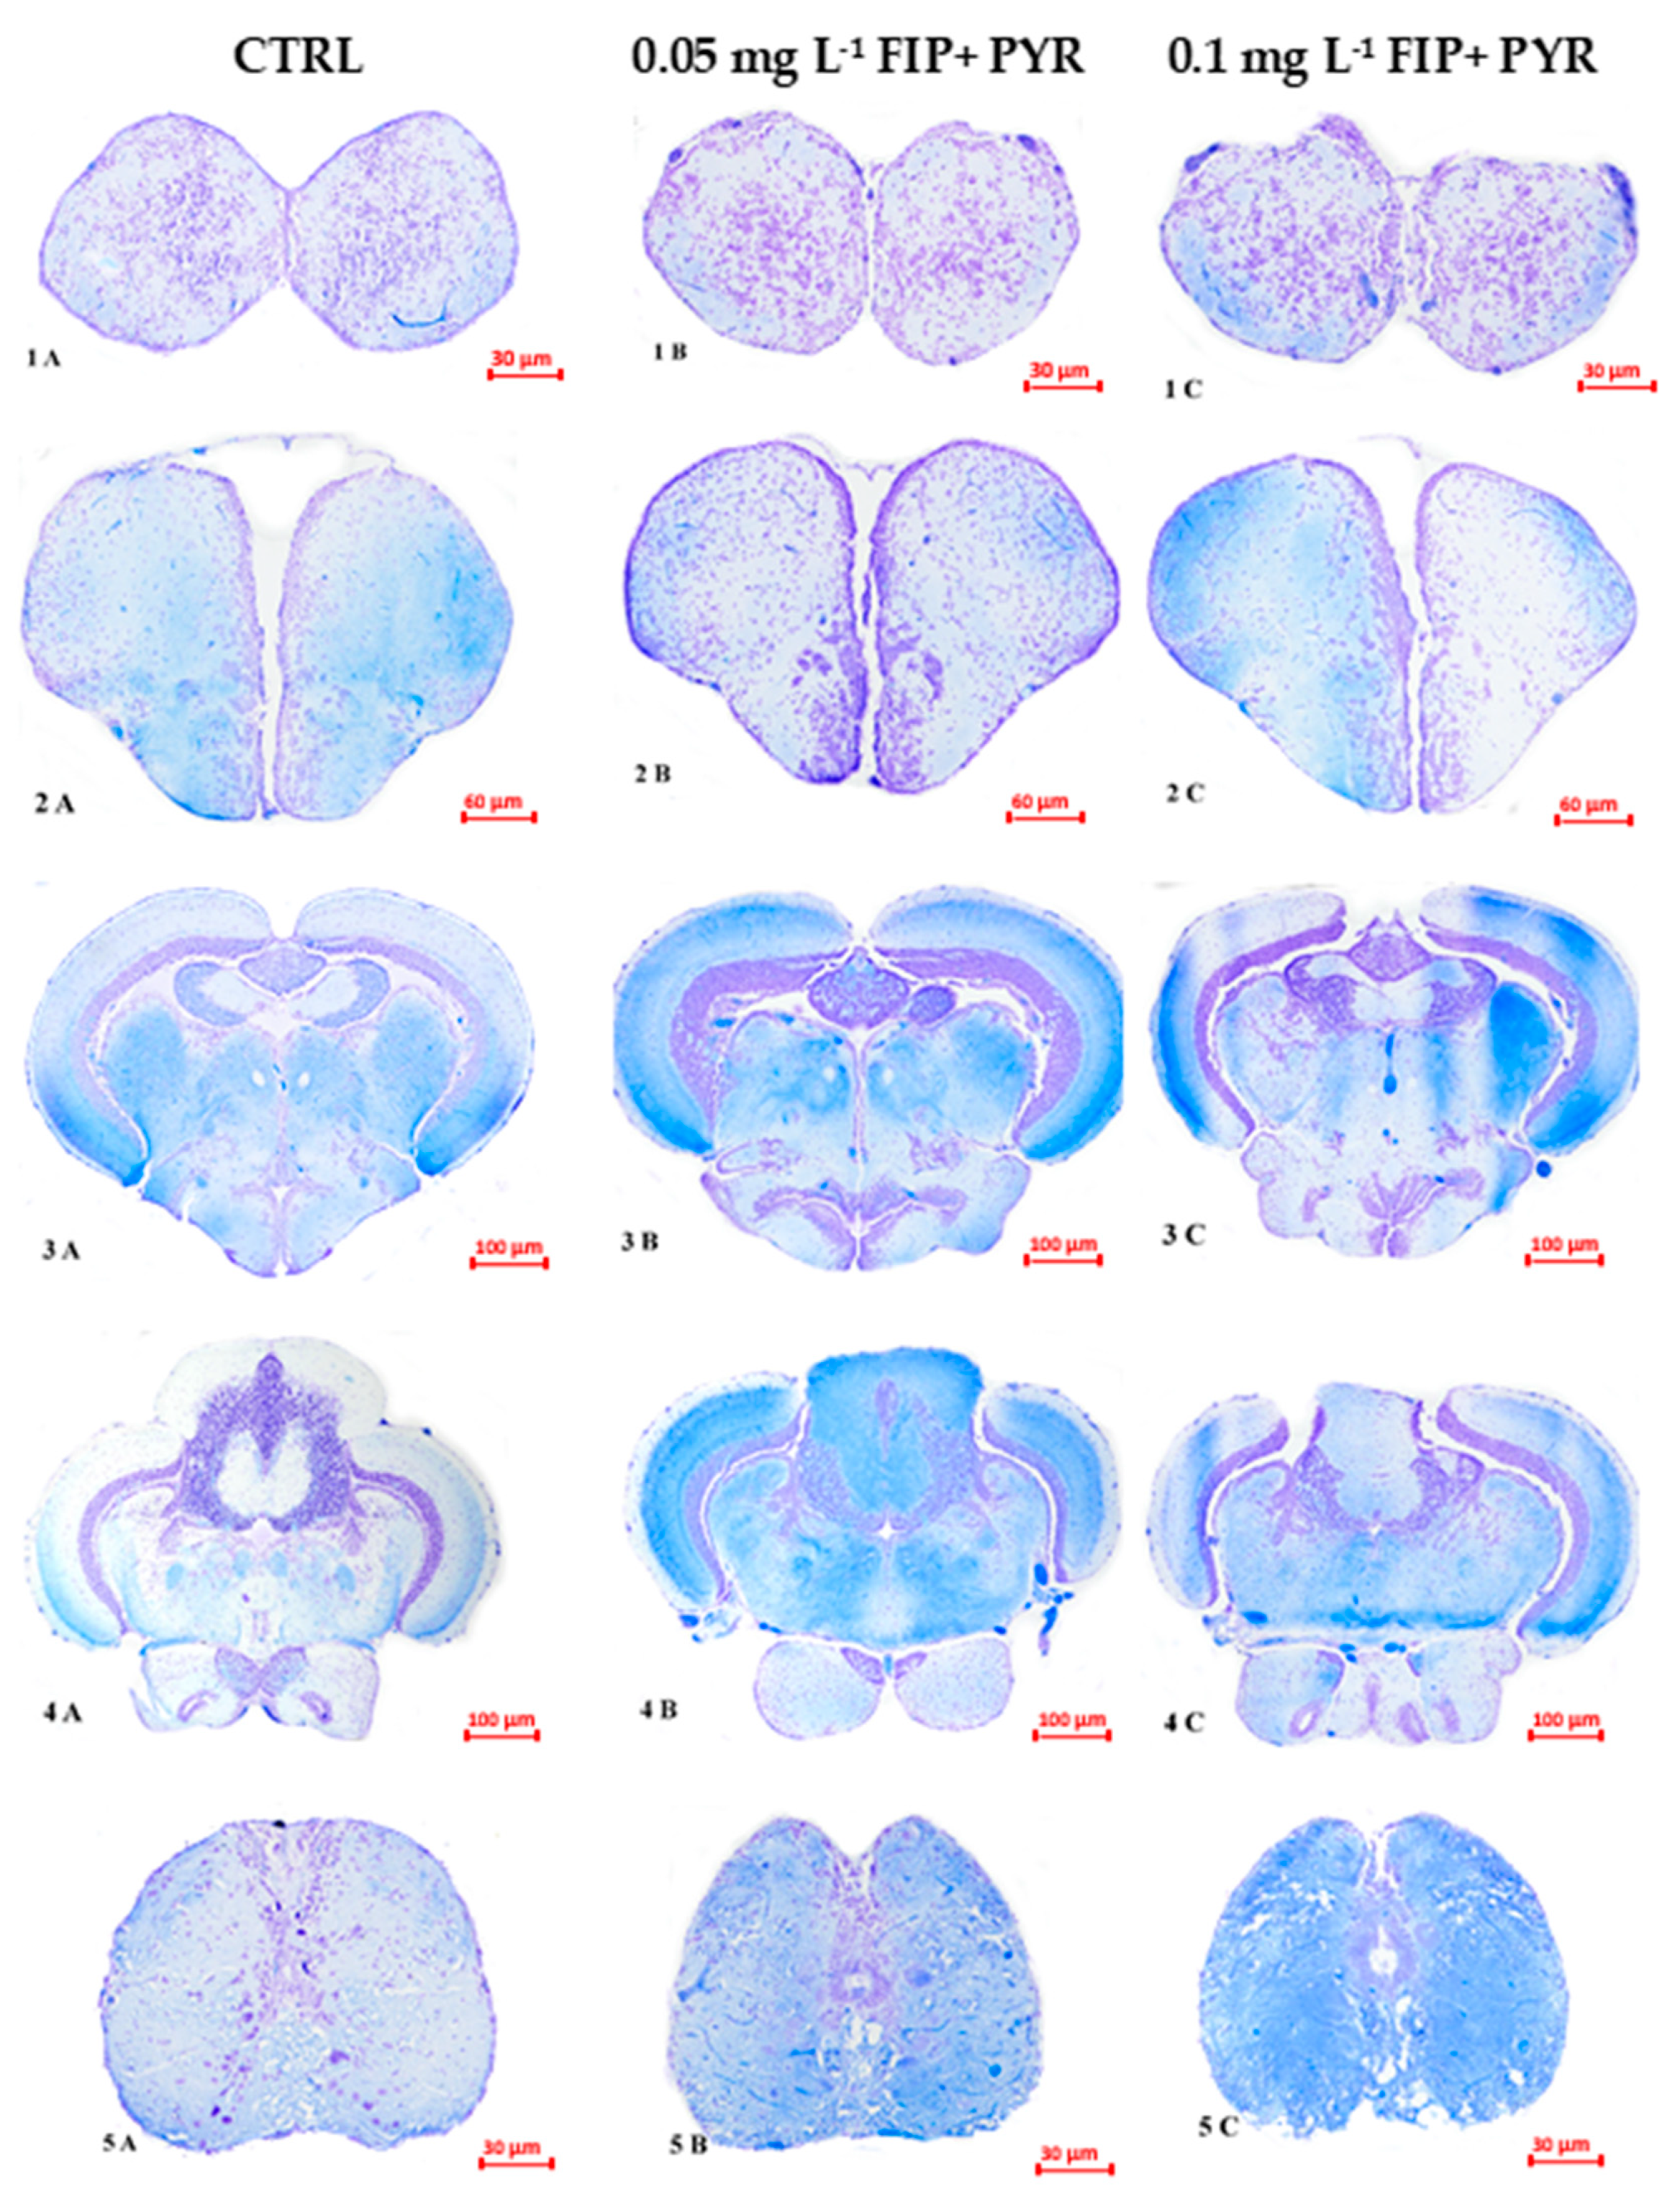

3.3. Histological Alterations

| FIP + PYR | zebrafish Danio rerio | 0.05 and 0.1 mg L−1 5 days | ↑locomotor activity ↑anxiety level ↑hemosiderin deposits dilated blood vessels and leucocyte infiltration in different brain sections | Present work |